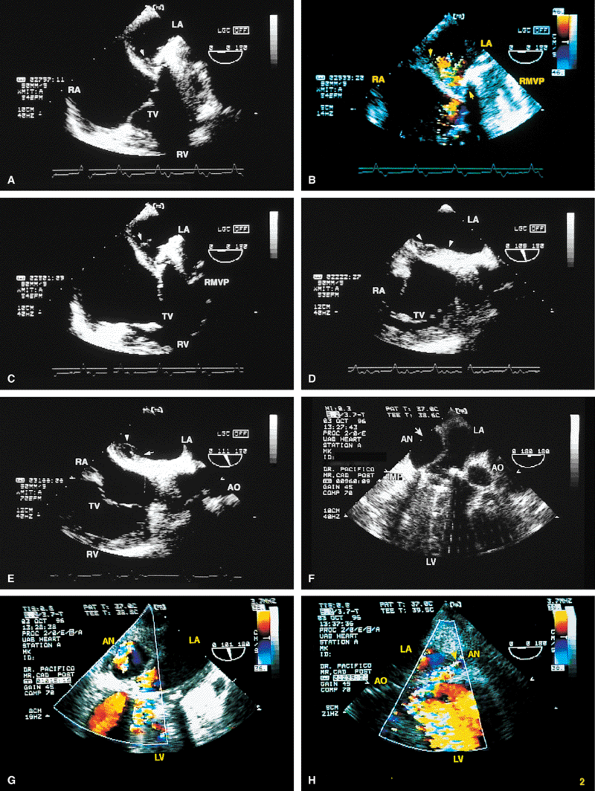

FIGURE 5.6. A–E. CarboMedics mitral prosthesis: dehiscence of left atrium (LA) wall. A. A small linear echo (vertical arrow) at the site of the paravalvular defect (horizontal arrow) consistent with suture material. B. Color Doppler examination shows a large paravalvular regurgitant jet originating at the site of the paravalvular defect (arrow) shown in A. C. An abnormal 1-cm linear echo (arrow) protrudes into the LA at the midinteratrial septal level. D,E. Multiplane views at 105° and 111° demonstrate a cavitary defect (arrows) involving the LA wall at the midinteratrial septal level, indicative of dehiscence, which explains the presence of the linear echo in the LA seen in C. F–H. CarboMedics mitral prosthesis (MP): LA pseudoaneurysm. F. A large pseudoaneurysm (AN; arrow) that developed following prosthetic replacement (MP, arrowhead) of the mitral valve.G,H. Color Doppler examination shows flow signals (arrowhead in H) moving from the left ventricle (LV) into the aneurysm cavity. AO, aorta; RA, right atrium; RMVP, reverberations from mitral valve prosthesis. (A–E reproduced with permission from Howard J, Agrawal G, Nanda NC. Transesophageal echocardiographic diagnosis of left atrial wall dehiscence. Echocardiography 1997;14:299–302. ) |

FIGURE 5.7. Bjork-Shiley mitral prosthesis: thrombus/pannus. A. A small echo density consistent with thrombus (T) is seen within the ring of the prosthesis (P). B. Its presence is confirmed by the flat diastolic velocity profile (arrows) and a high peak pressure gradient (16 mm Hg) across the prosthesis, consistent with obstruction. C–K. Another patient with a thrombosed Bjork-Shiley mitral prosthesis. Note the spontaneous contrast (SC) echoes in the left atrium (LA) in C, G, and J. I. A thrombus (TH) is well seen on the atrial aspect of the prosthesis (PMV) imaged with a probe in the esophagus, whereas the thrombus on the ventricular aspect is best visualized during transgastric examination (I).Another thrombus (TH) is present in the left atrial appendage (LAA) (G). Color Doppler–directed continuous wave Doppler reveals a very flat diastolic velocity profile with a very high peak velocity of 305 cm/sec, indicative of very severe flow obstruction. K. The arrowhead in J shows prominent flow acceleration on the atrial aspect of the prosthesis. R, prosthetic ring. L. Another patient with a Bjork-Shiley prosthesis. In this patient, the echo density on the ventricular aspect of the prosthesis (P) was found at surgery to be a pannus (PAN) rather than a thrombus. Spontaneous echo contrast (SEC) was present in LA. M. Gross specimen of a thrombosed mitral prosthetic valve. AO, aorta; LV, left ventricle; RV, right ventricle, spontaneous contrast. |